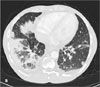

Therapy with intravenous ceftriaxone and azithromycin was started for presumed community-acquired pneumonia, and the patient was isolated as a precaution. Her clinical condition did not improve with antibiotic and supportive treatment. No acidfast bacilli were isolated from sputum samples. A CT scan of the

chest showed extensive bilateral basilar pneumonitis (B). Multiple small cavities in both lungs were also noted. A subsequent bronchoscopy with lavage and bronchial washing isolated Serratia marcescens.